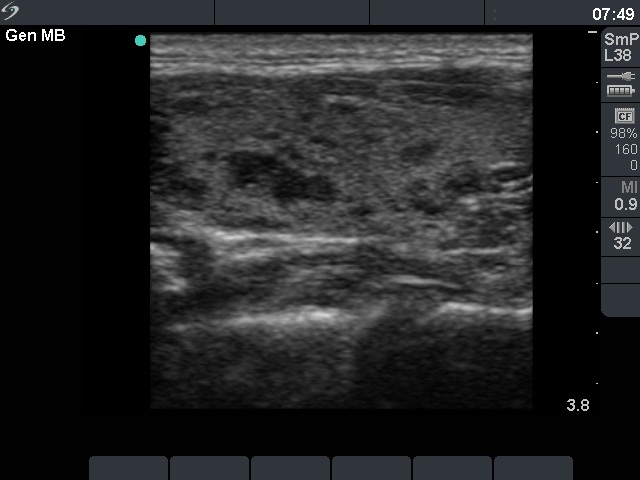

Ultrasonography: there were multiple small hypoechogenic areas in both lobes. The borders of these lesions were irregular. The US pattern corresponded to autoimmune thyroiditis.